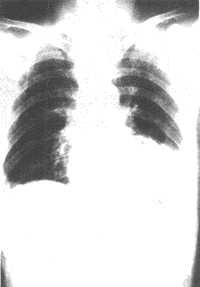

2、胸部X線

常規胸片常不能確定PE的診斷,大約10%肺栓塞的患者有陽性表現,但缺乏特異性。主要表現為區域性肺血管紋理纖細、心臟擴大、肺動脈高壓、胸腔積液、間質水腫、肺不張、肺浸潤性改變、半側膈升高。